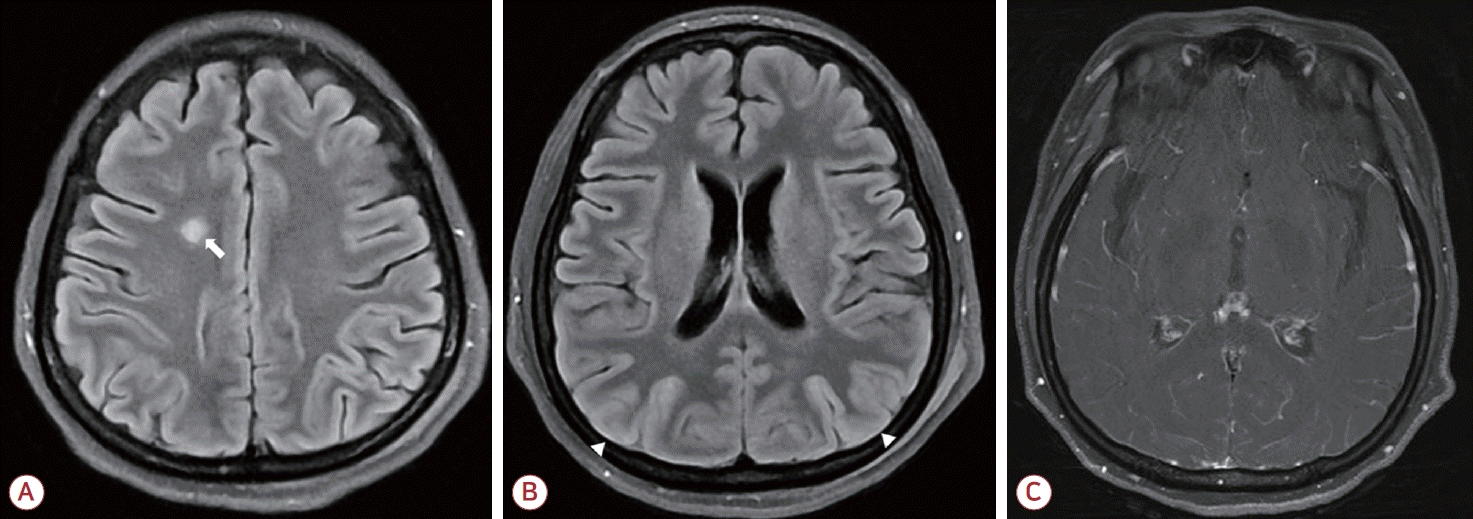

Figure 1.

Brain MRI at admission day 4. (A) Right frontal lobe lesion on FLAIR image (arrow). (B) Diffuse cortical swelling, especially on bilateral parieto-occipital lobe (arrowheads) on FLAIR image. (C) Diffuse leptomeningeal enhancement on T1-weighted image with gadolinium enhancement. MRI; magnetic resonance imaging, FLAIR; fluid attenuated inversion recovery.